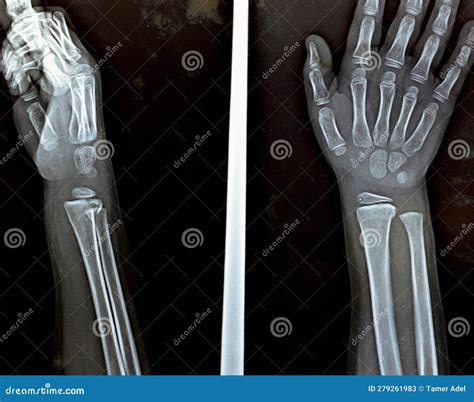

An MRI wrist joint scan is a non-invasive imaging technique that uses magnetic fields and radio waves to produce detailed images of the wrist. Unlike X-rays, which primarily show bones, MRI scans can visualize soft tissues such as ligaments, tendons, and cartilage. This makes MRI particularly useful for diagnosing conditions that affect these structures, such as fractures, ligament tears, and arthritis.

• Fractures: MRI can detect fractures that may not be visible on X-rays, especially in the early stages.

• X-Rays: Useful for detecting bone fractures and certain types of arthritis.

• CT Scans: Provide detailed images of bones and can be useful for detecting fractures and bone abnormalities.

Each of these techniques has its own advantages and limitations, and the choice of imaging method will depend on the specific condition being investigated.